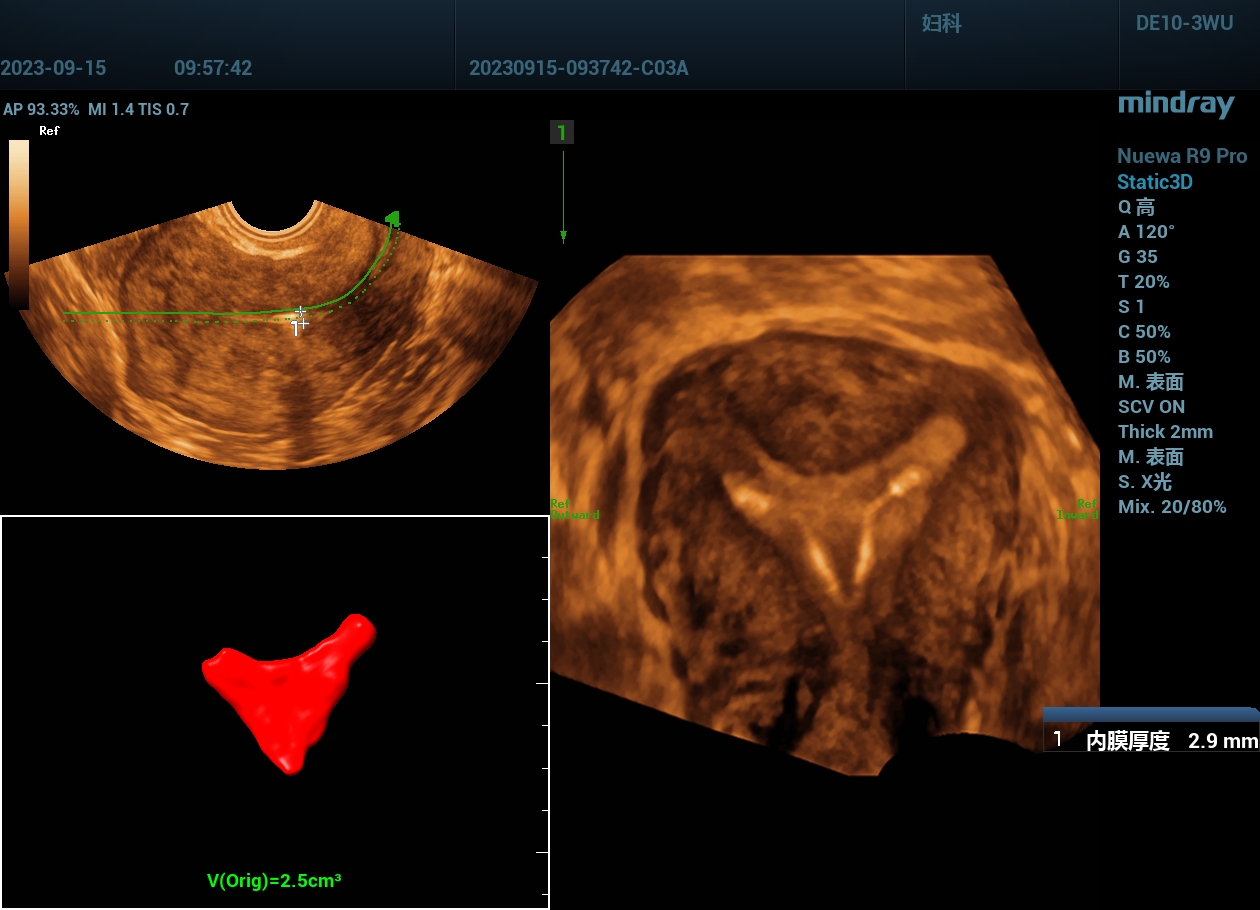

不完全性纵隔子宫声像图:子宫外形正常,但宫底横径较宽;宫底水平横切面显示子宫内部纵隔,其两侧各见一宫内膜回声;三维超声子宫冠状切面成像显示不完全纵隔子宫为Y形。